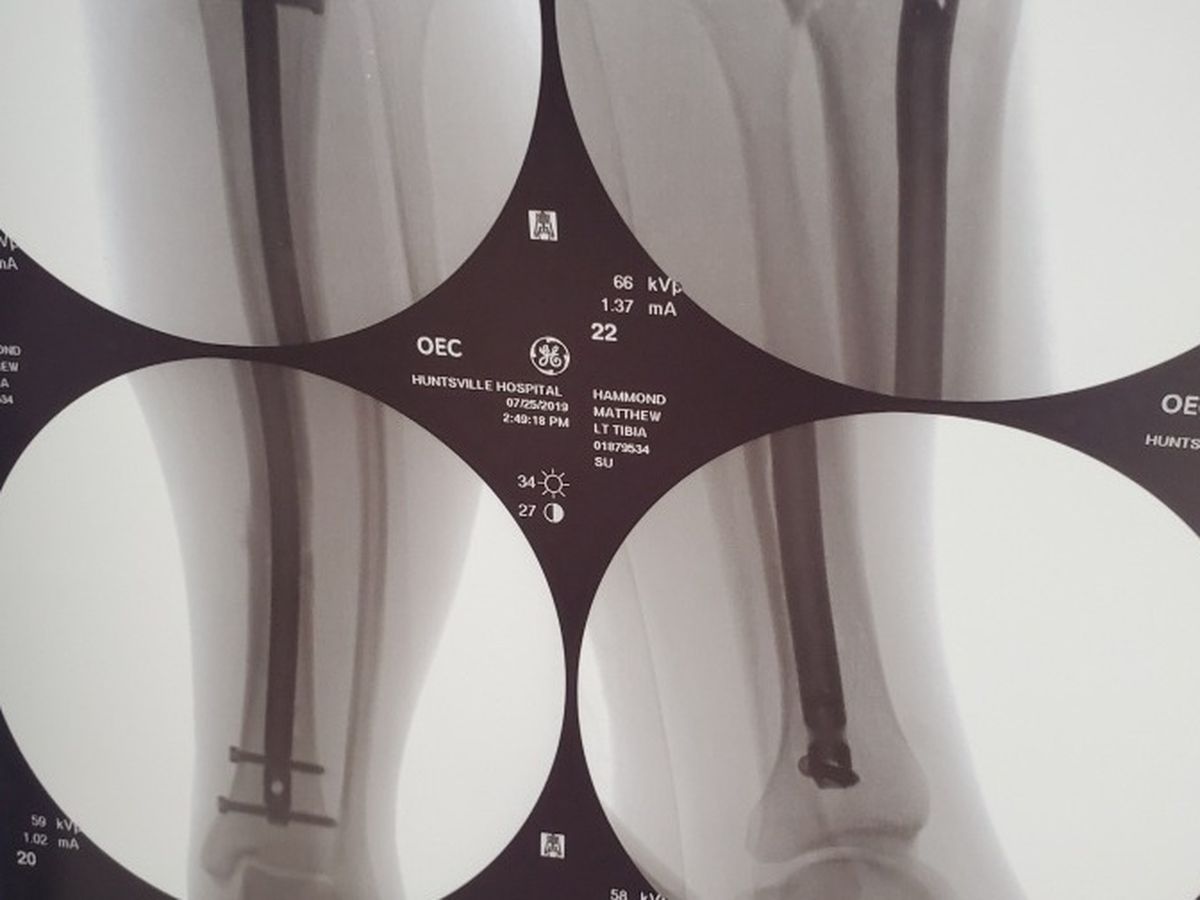

The accident left him with a concussion and a severely broken left leg.   Doctors placed a rod and several screws in the broken leg Thursday morning and as of Sunday Matt is finally home.